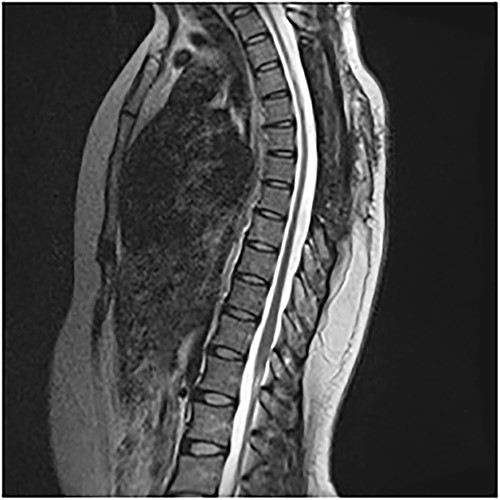

On the first postoperative day, neurological examination revealed that power had returned to the preoperative state and her pain had significantly reduced. She was commenced on physiotherapy and on the third day postop, her limb pain had completely disappeared, while power had improved to 4 in the right lower extremity muscle groups. She was discharged on the fifth postoperative day and was to be seen in the out-patient clinic. Postop images showed total resection of cyst and gradual re-expansion of the spinal cord (Fig. 6). At 12-week follow-up, she had complete resolution of her preoperative symptoms and had returned to full functional independence.